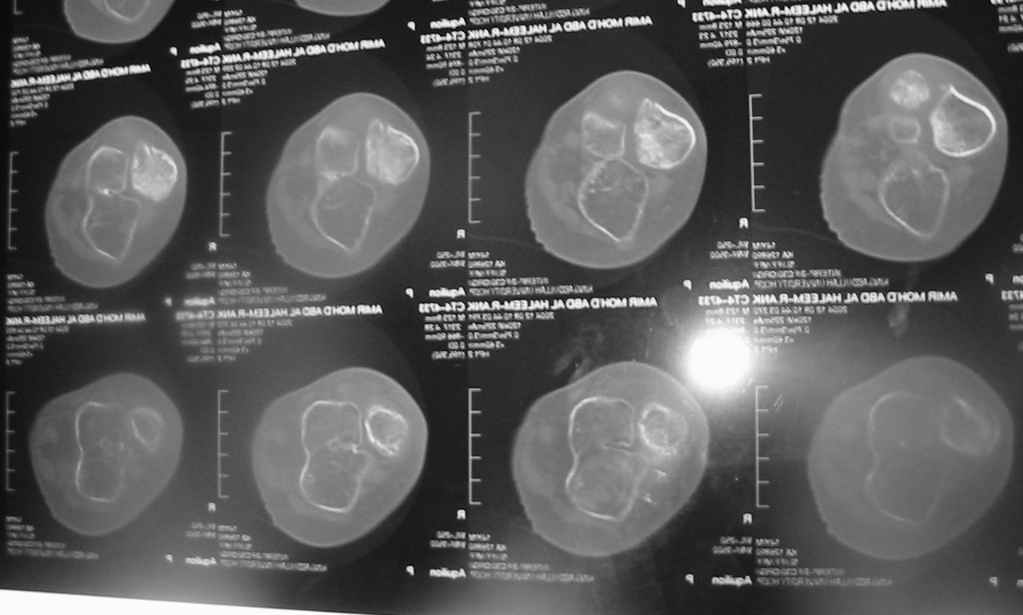

Uvazaemie Docotora, Podskazete, pozalusta, kak mozno pomoch' etomu 13 letnemu bolnomu,

s tiazeloi vrazdennoi patologiei goleny, golenostopnogo sustava i stopy, Snimky i foto prelagaiotsa.....